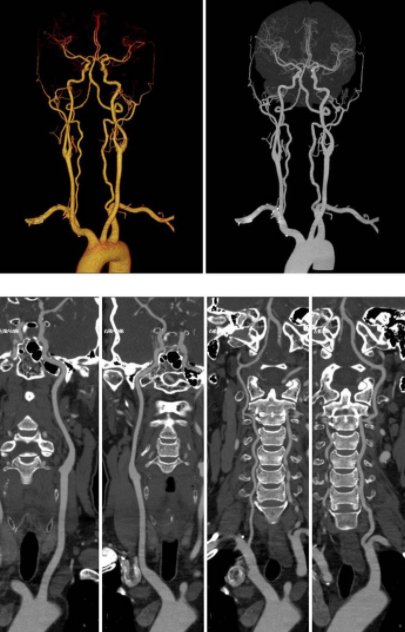

头颈部动脉CTA能准确地对头颈部血管病变作出诊断,适用于头颈部血管畸形、血管壁斑块及血栓形成、动脉血管狭窄闭塞、动脉瘤及颅内肿瘤的发现。